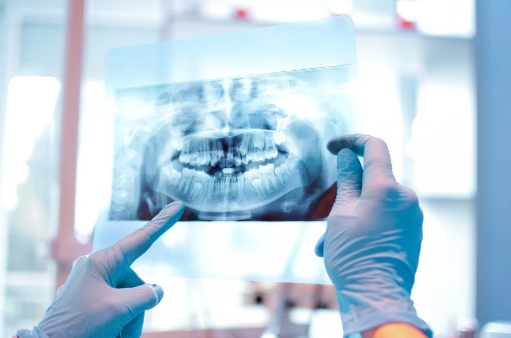

Na prática, a principal função do profissional em Radiologia em Odontologia é a manipulação de máquinas, interpretação e descrição radiográfica. O técnico em radiologia que atua na área fica responsável pela operação de equipamentos destinados à geração de imagens radiográficas intra e extra-bucais. Já o tecnólogo chega a produzir laudos que descrevem as imagens e são encaminhados para ortodontistas. A partir dessas informações são desenvolvidos os tratamentos em diversos ramos da Odontologia.

Um técnico radiologista passa por uma formação baseada no conhecimento prático. A especialidade deste técnico é na área Radiodiagnóstico , na qual suas funções são práticas e operacionais como por exemplo: colocar o paciente na posição correta, realização de exames por imagens, fazer a verificação  das fontes emissoras de radiação, entre outras funções relacionados a operação do equipamento de radiologia.